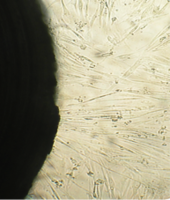

6 серия экспериментов. Образец исследуемого материала (аллогенный ГАП серии «Лиопласт»® массой 2 мг) помещали на дно культуральной чашки, после чего высевали фибробласты в стандартной концентрации.

Щелочной материал резко ухудшает прикрепление фибробластов к дну культуральных чашек (рис. 35) на всей его площади, вместе с тем прикрепившиеся клетки имеют четкие границы, нуклеолемма четко контурирует, цитоплазма гомогенная, без патологической зерностости, вакуолей и включений.

Рис. 35. Выраженная пролиферация, восстановление плотности монослоя.

В последующие дни и до конца наблюдения плотность монослоя  в отдаленной от образца зоне нарастает даже несколько быстрее, чем в контроле, клетки сохраняют обычную для фибробластов в культуре морфологию.